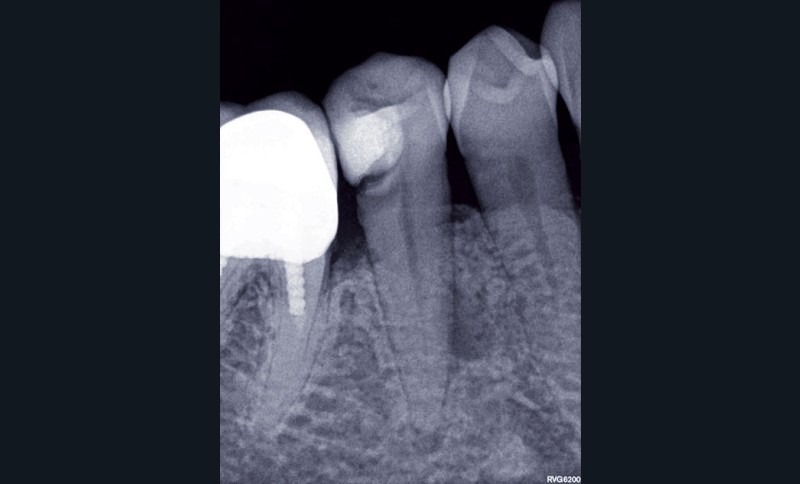

1. Une radiographie rétro-alvéolaire centrée sur 45 met en évidence une reprise de carie sous la restauration en composite et une lésion inflammatoire périradiculaire d’origine endodontique (LIPOE). Le test de vitalité est négatif.